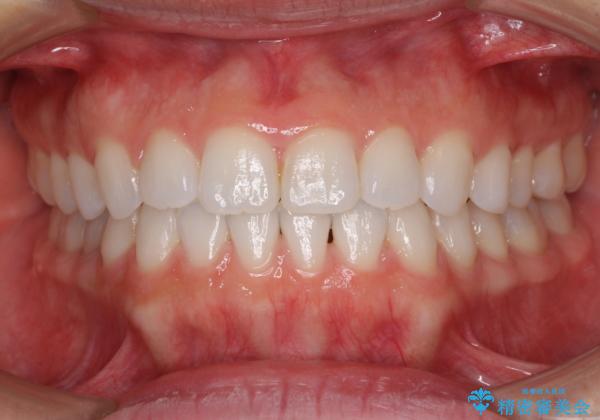

インビザラインによる反対咬合の改善は、上の歯が下の歯を乗り越えていく期間に咬み合わせが非常に不安定となり、治療が長期化することがあります。

こちらの患者様も、一時的に前歯でしか咬めない時期がありましたが、比較的早く咬み合わせが安定し、1年ほどで治療を終えることができました。